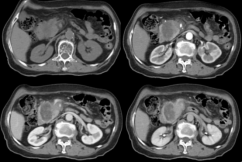

(2)腺癌CT表现:胰腺局部增大、肿块形成,多呈等或稍低密度,增强扫描多呈低密度而显示更清楚;胰头Ca常伴胰体尾萎缩;胰腺钩突变为隆凸或球形,提示钩突肿瘤;胰管和胆管扩张。

截屏2022-10-06 18.58.49

胰腺癌MRI表现:横断面所见与CT相同。T1WI肿瘤呈低或等信号,T2WI肿瘤呈稍高信号;MRCP能清晰显示梗阻扩张的胰管和胆管。

截屏2022-10-06 18.59.46

4胰岛细胞瘤:多数肿瘤较小,增强CT富血供,动脉期强化明显高于正常胰腺组织,但静脉期肿瘤密度与正常胰腺组织接近。

截屏2022-10-06 19.03.37